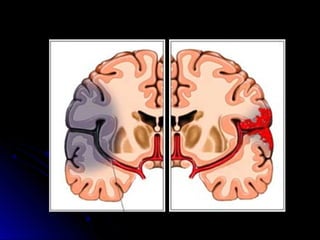

ISQUEMICOS (85%)

tipos :

HEMORRAGICOS (15%)

1.I nt raparenquimat oso

s

2. Hemorragia

Subaracnoidea

HemorragiaIsquemia (infarto)

Enfermedad Cerebro Vascular

ISQUEMICA